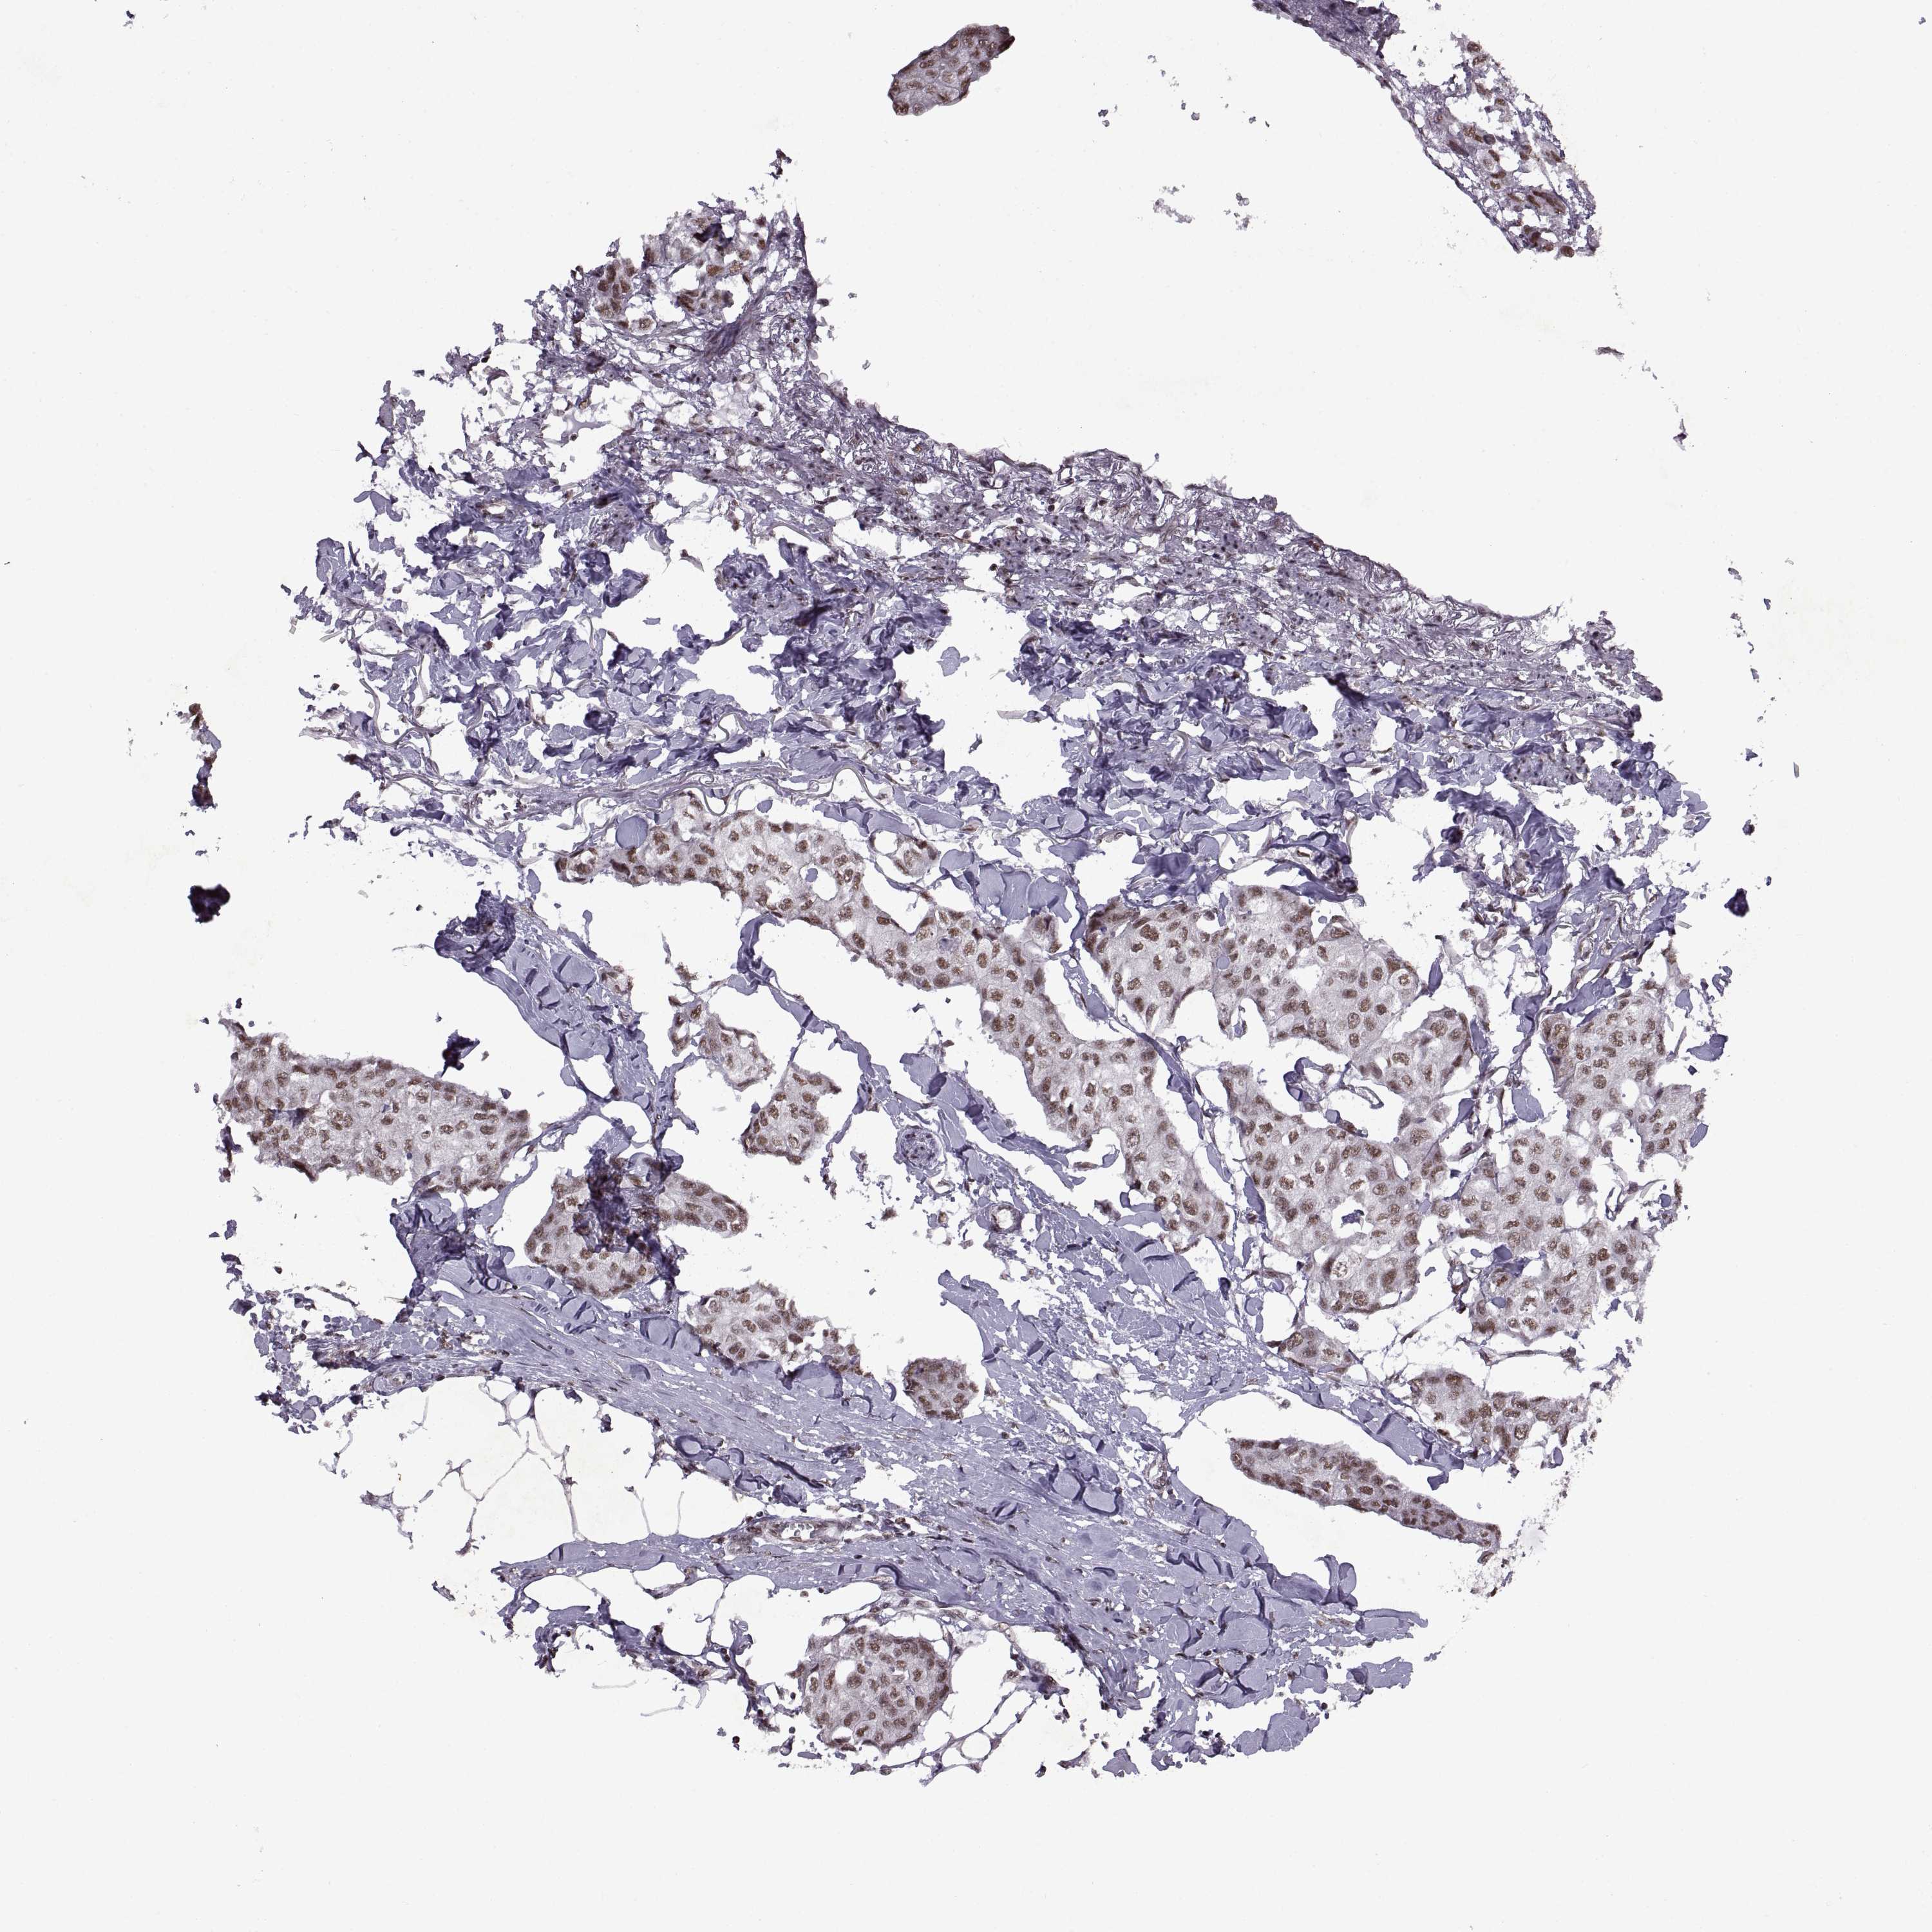

BRCA TCGA BRCA VALIDATION PROTEIN EXPRESSION